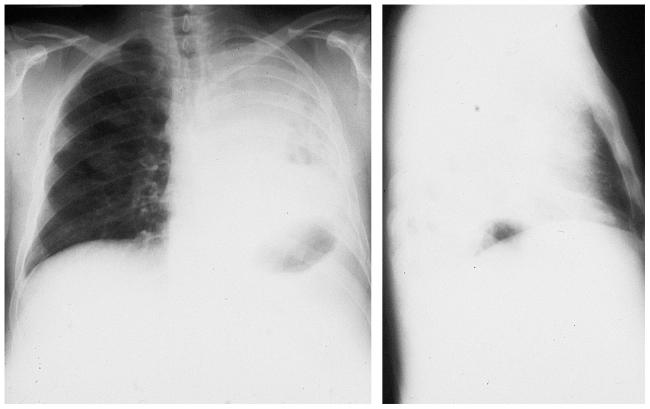

Компрессионный ателектаз

По-другому компрессионное спадение легкого называется коллапсом и возникает при сдавливании газами или жидкостью извне (экссудатом, транссудатом, кровью, фиброзной тканью). Компрессионный механизм развития ателектаза имеет более оптимистичный прогноз при лечении, так как в патогенезе отсутствуют эндобронхиальные факторы — спадение легкого не вызывает выраженной задержки лимфы или полнокровия.

На рентгеновских снимках выявляют следующие признаки, указывающие на спадение легочной ткани:

Однородное затемнение в области поражения. Размеры тени зависят от вида ателектаза: при долевом выявляется обширное затемнение, при сегментарном — в виде клина или треугольника, расположенного вершиной к корню легкого, дольковые ателектазы множественные и похожи на очаговую пневмонию. Дистензионный ателектаз расположен низко, около диафрагмы, имеет небольшие размеры и вид поперечных полос или темных дисков. Смещение органов: при компрессионном ателектазе смещение наблюдается в здоровую сторону, так как на стороне поражения давление больше, при обтурационном, наоборот – смещение будет в сторону ателектаза, так как на стороне поражения нарастает притягивающее отрицательное давление. Подъем купола диафрагмы – это видно по расположению печени.